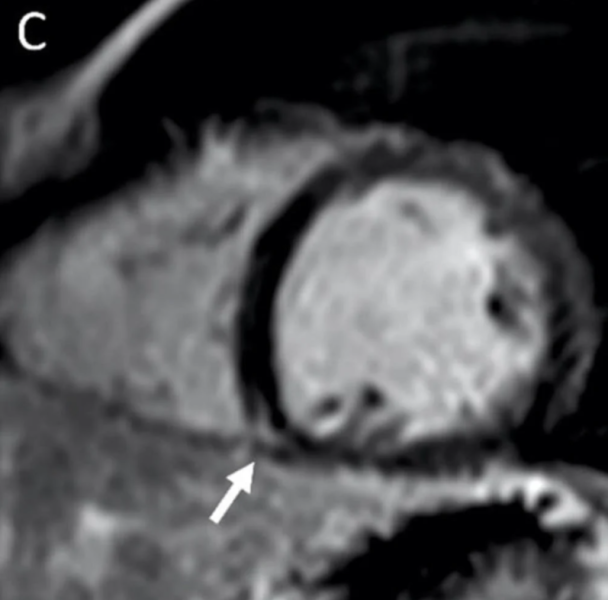

This photo gallery shows the variety of radiological presentations of COVID-19 (SARS-CoV-2) in medical imaging, including computed tomography (CT), radiograph X-rays, ultrasound, echocardiograms and magnetic resonance imaging (MRI). The radiology images show examples of typical COVID pneumonia in the lungs and the numerous complications the virus causes in the body in multiple organs, including the brain, kidneys, heart, abdomen and vascular system.

The images were collected from physicians, study authors, universities and hospitals, the National Institutes of Health (NIH), the Radiological Society of North America (RSNA), the American College of Radiology (ACR), Centers for Disease Control and Prevention (CDC) and radiology technology vendors.